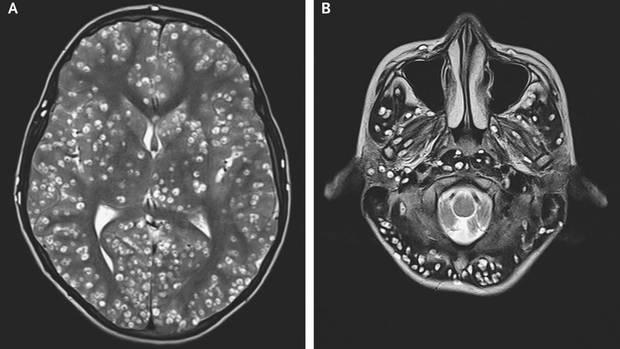

The MRI Scans of the brain of the patient showing the injury caused by the tapeworm

MRI shows brain damage after infection with tapeworm

In the case of an MRI of his head, the doctors discovered damage in the cerebral cortex and other Parts of the brain. This was due to cysts that had formed as a result of a tapeworm infection – that is to say: The larvae of the parasite were stored in the brain. In ultrasound examinations of the right eye, and testis more cysts were discovered.